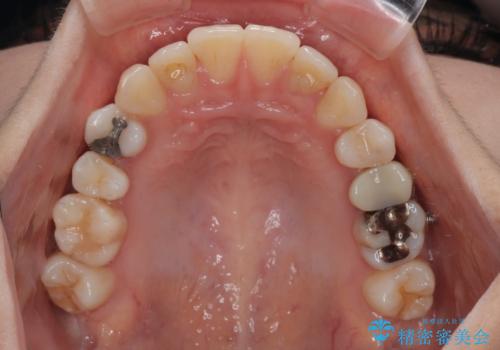

- 上下前歯のデコボコとクロスバイトを気にして来院された患者様です。

治療済みの処置歯が多いため、インビザラインを用いて矯正治療を行うこととしました。

下顎臼歯部にブリッジが装着されており、移動不可のため、IPR(歯と歯の間を削る)と歯列全体を拡大させることで、歯並びを整えていくこととしました。